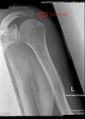

هناك ثلاثة أنواع متميزة من ناحية التشكّل (المورفولوجية) للأخرم ، ووجود علاقة ارتباط متلازم بين هذه الأشكال وتمزق عضلة الكفة المدورة:[2]

النوع الانتشار زاوية الميل

الوحشي

تمزق

عضلة الكفة المدورة

مفلطح 17.1% 13.18 3.0%

مقوّس 42.9% 29.98 24.2%

خطاّفي 39.3% 26.98 69.8%